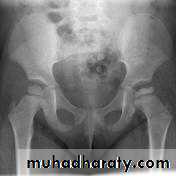

DEVELOPMENTAL DYSFLASIA OF HIP (CONGENITAL DISLOCATION OF THE HIP)

• An abnormally lax joint capsule allows the femoral head to fall out of the acetabulum, leading to deformation.• Predisposing factors for the development of CDH are:

• * Abnormal ligamentous laxity (effect of estrogen; fema1e:male = 6:l)

• * Acetabular dysplasia .

• CDH occurs most commonly (70%) in the left hip. Bilateral involvement is seen in 5%.

• Radiographic features

• US (commonly used today) at 1-3 months

• * Normal femoral head is covered at least 50% by acetabulum , In CDH < 50% of femoral head is covered by acetabulum .

Plain film

At 3-6 months :By doing special veiw (Von Rosen veiw )by abduction of the thigh 45 degree and internal rotation .

In DDH the lines that drown through the femura will meet in higher level than the normally should at lumbosacral joint .

6 months and later

* AP veiw ( femural epiphysis are visualized ):* Superolateral displacement of proximal femur (disturbed shenton’s line )

* Increase in acetabular angle

* Small capital femoral epiphysis

Femoral head is located lateral to Perkin's line

* Other features that are sometimes present

Abnormal sclerosis of the acetabulum

Shallow acetabulum

Formation of a false acetabulurn

Delayed ossification of femoral head